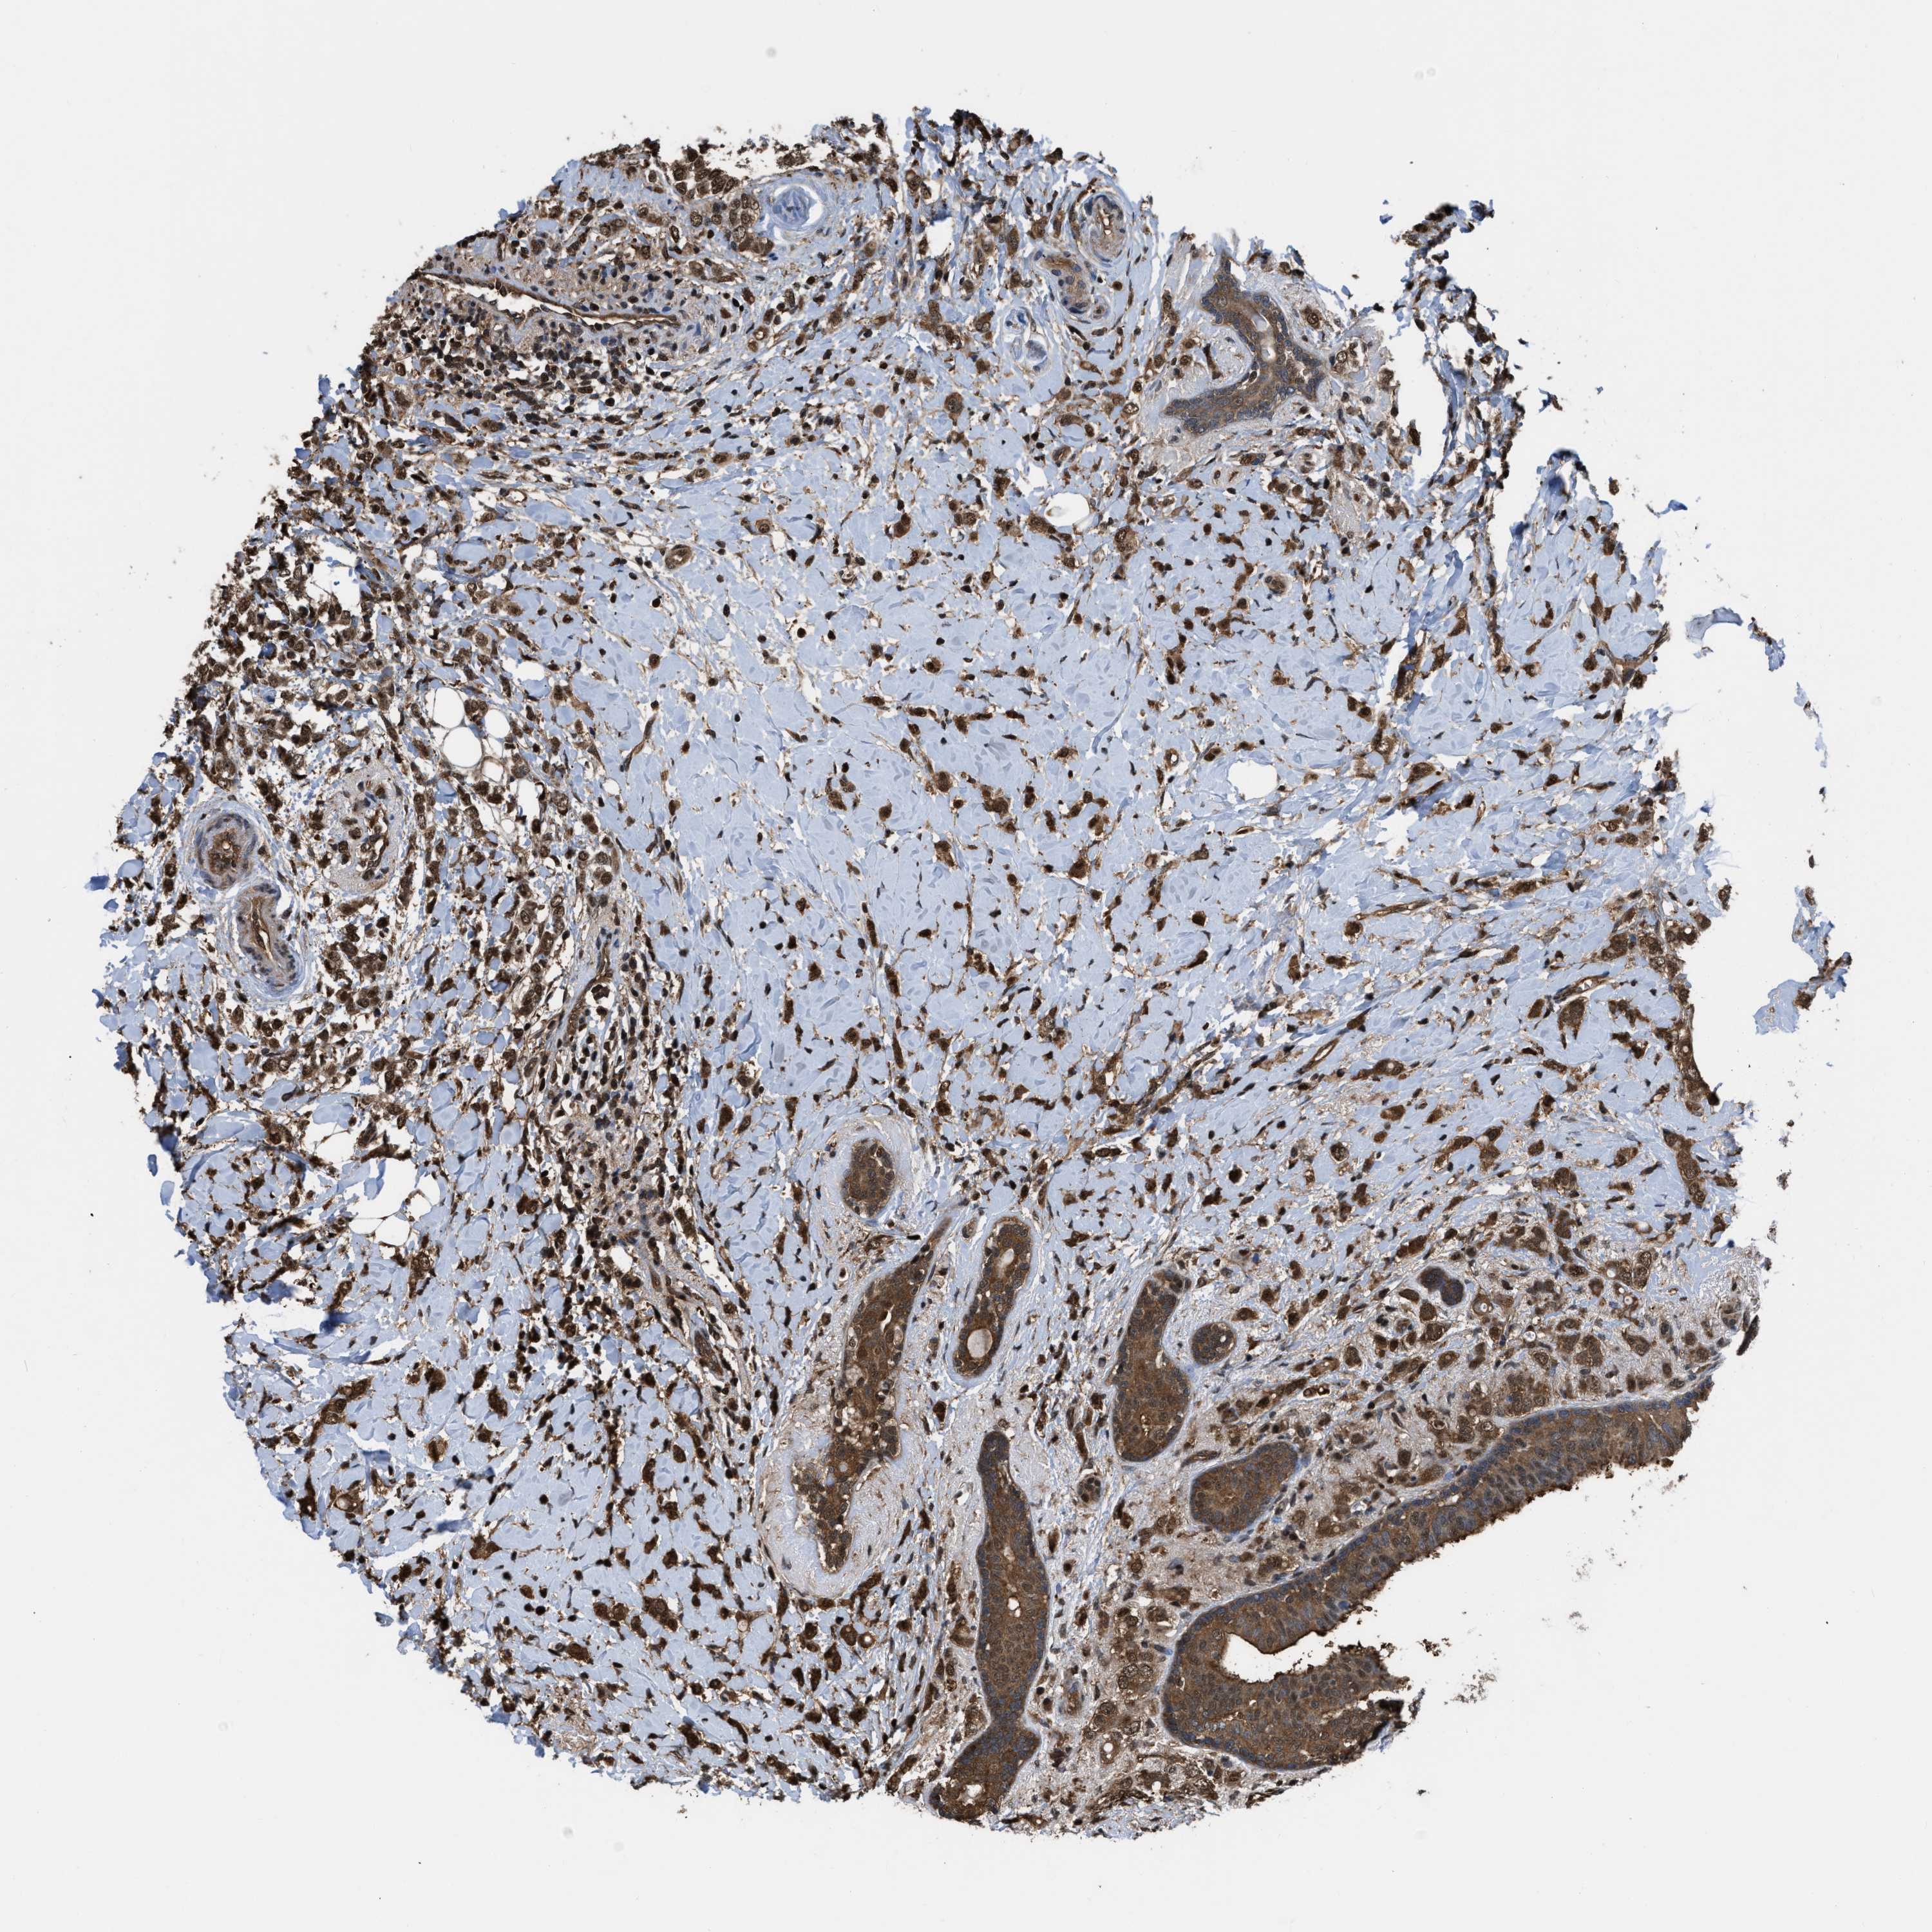

CANCER BREAST CANCER Show tissue menu

BRCA TCGA BRCA VALIDATION PROTEIN EXPRESSION